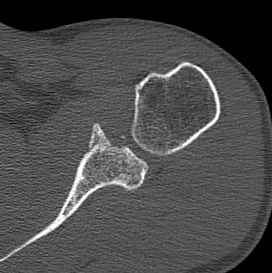

CT scan

Bony bankart

Bony bankart 3D CT with humeral head subtraction

Hill Sachs